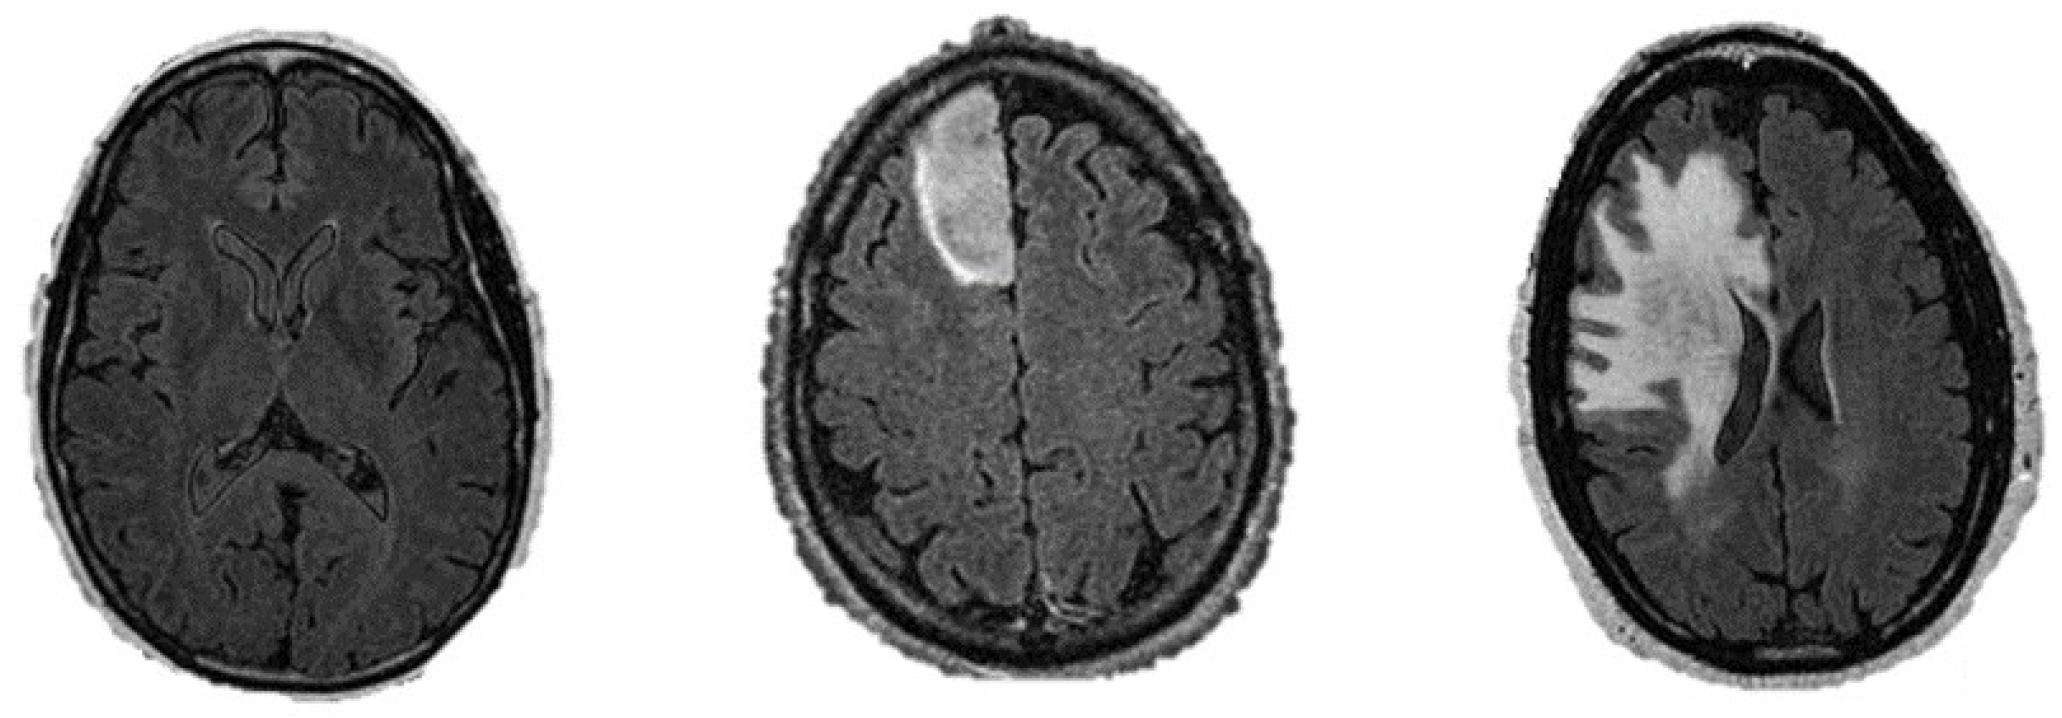

2.1. Classification of Brain MR Images

- MR brain images of healthy subjects.

- MR brain images of glioma patients having low-grade glioma tumor.

- MR brain images of glioma patients having high-grade glioma tumor.